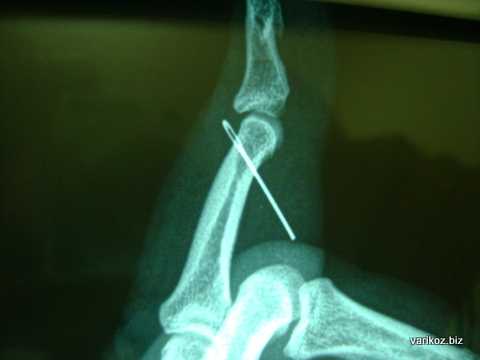

На фото - инородное тело - обломок иглы в мягких тканях пальца кисти.

Обнаружить и уточнить расположение контрастных инородных тел при рентгенологическом исследовании значительно проще, чем распознать неконтрастные тела, внедрившиеся в ткани. Рентгенография кисти обязательна как в том, так и в другом случае, так как иногда удается уловить на пленке легкую тень и от рыбьей кости, и от стекла или деревянной занозы. Предложено много различных способов уточнения локализации инородных тел, но для кисти наиболее простыми и надежными являются рентгенография в трех проекциях и рентгеноскопия. При этом отыскивается точка наибольшего погружения инородного тела при надавливании, подводится к инородному телу стерильная игла, и тогда определяется удобный доступ. Поэтому при рентгенографии всегда рекомендуется присутствие хирурга. Прямой снимок делается в положении кисти, соответствующем тому, какое она будет иметь на операционном столе; второй снимок — в строго боковой проекции, он дает представление о глубине залегания инородного тела.